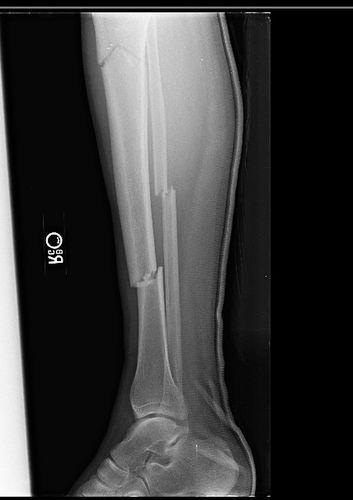

Phalanx Fractures - Hand - Orthobullets from upload.orthobullets.com